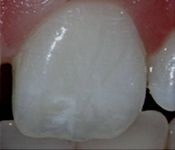

Pictured: Necrosis and 3 Year Recall with Complete Root Formation after Revascularization

Our patient developed necrosis of tooth #9 caused by intrusive luxation. We opted to treat with revascularization with triple antibiotic and MTA. In our 3 year recall, the patient had achieved complete root formation.